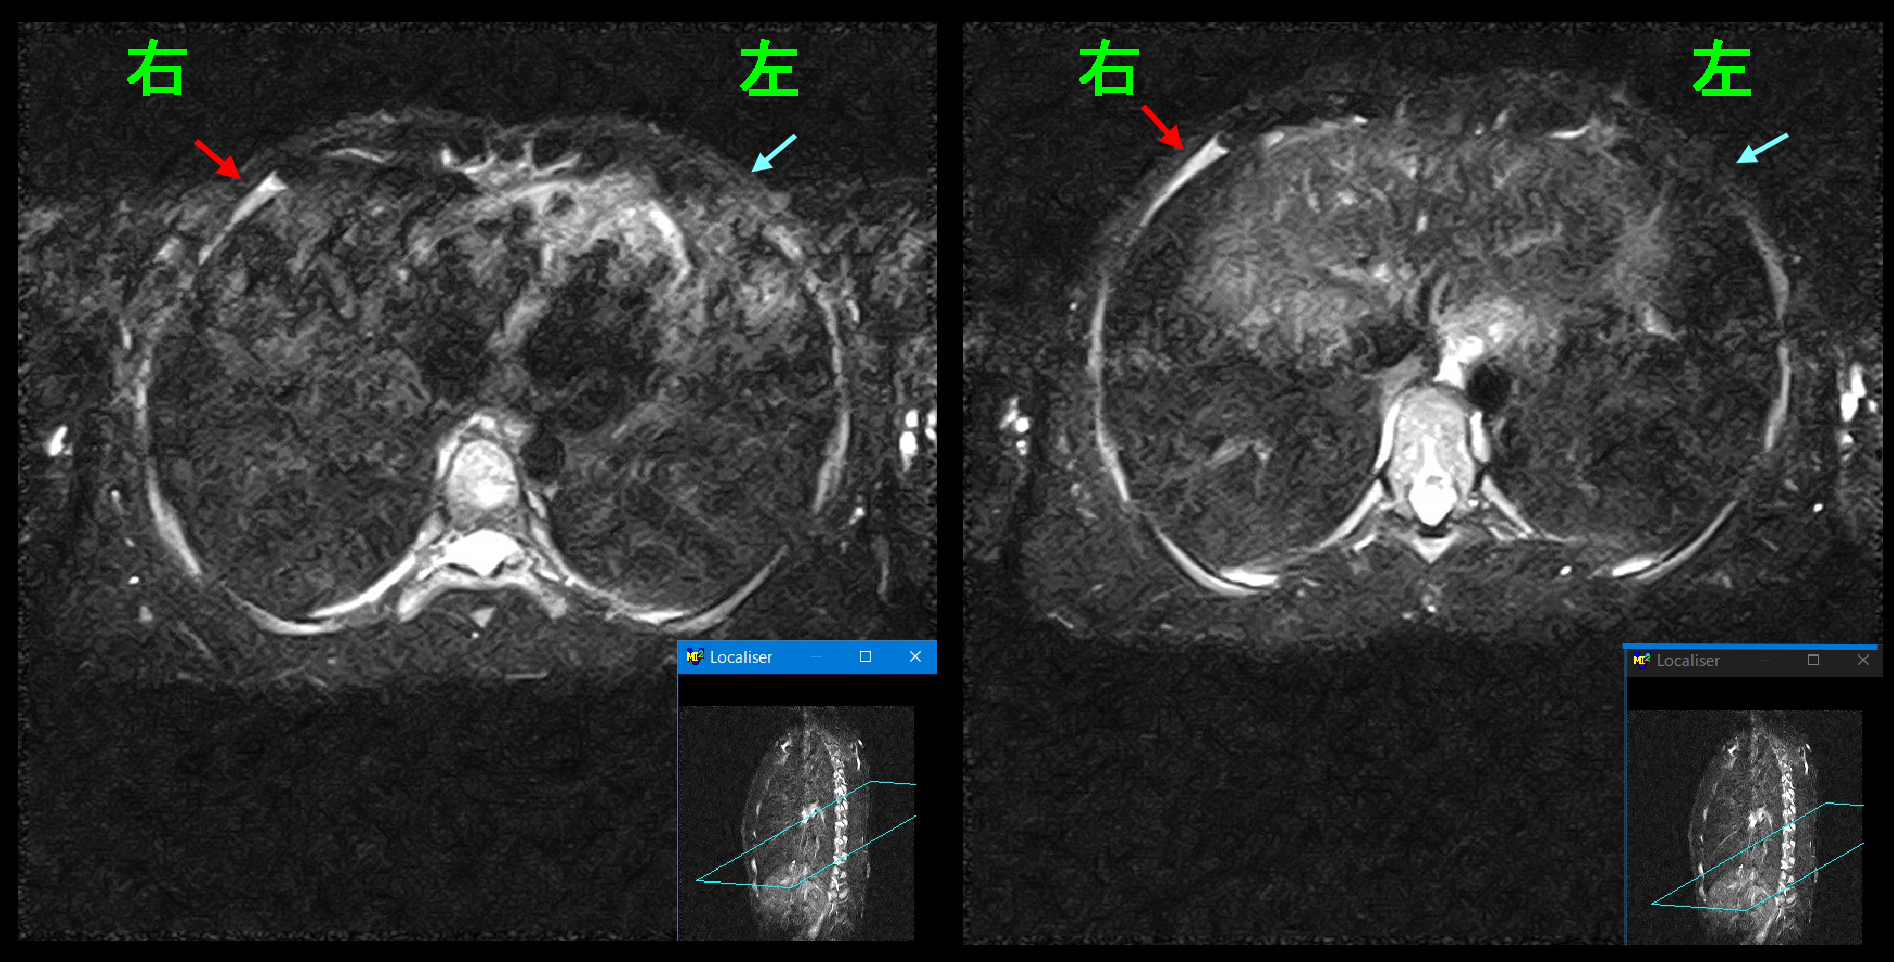

レントゲン像では異常はありません。最も考えられる診断としては右肋骨の疲労骨折ですと説明し、疲労骨折はMRI検査でしか診断できないことを伝えると、患者さんは希望されたため、

Xp.jpg

1月18日にMRI検査を施行しました。MRI検査で肋骨の疲労骨折の所見が確認されなければ、胸椎の椎間板ヘルニア等を疑うこととなります。